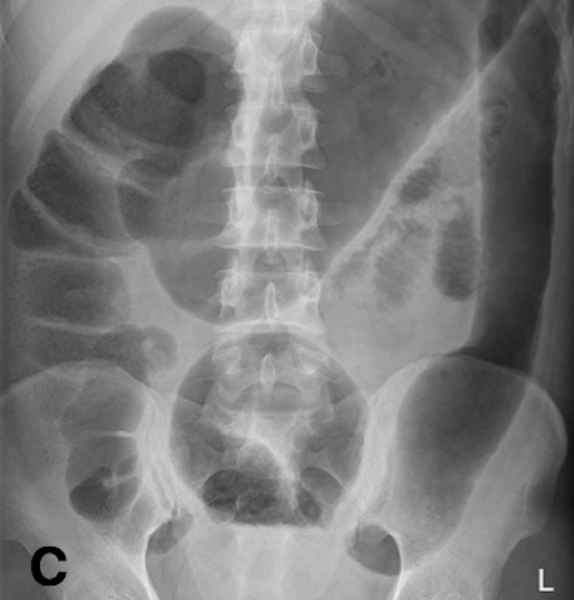

What is pictured here?

What are the AXR features of UC flares?

Describe toxic megacolon as a complication of UC?